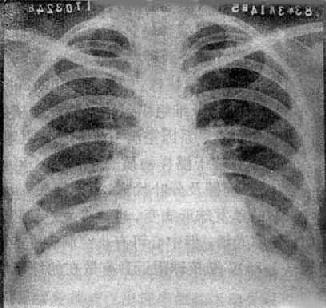

X线表现是病变多发生在两肺中、下野的内、中带。支气管及周围间质的炎变表现为肺纹理增多、增粗和模糊。小叶性渗出与实变则表现为沿肺纺理分布的斑片状模糊致密影,密度不均(图3-1-18)。密集的病变可融合成较大的片状。病变广泛可累及多个肺叶。小儿患者常见肺门影增大、模糊并常伴有局限性肺气肿。

图3-1-18 支气管肺炎

肺门影增大,肺纹理增强、模糊,中、下肺

野可见沿肺纹理分布的斑片状模糊致密影